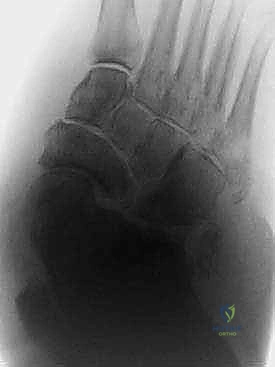

الخطوة الثالثة: استئصال العظام البارزة (Exostectomy)

إذا كان هناك بروز عظمي في باطن القدم يسبب قرحة مزمنة (ولكن المفصل مستقر نسبياً)، قد يكتفي الجراح بإزالة هذا البروز العظمي وتنعيم السطح لحماية الجلد من التآكل المستقبلي.

الخطوة الرابعة: إعادة بناء وتثبيت المفاصل (Arthrodesis)

هذه هي المرحلة الأهم، حيث يتم دمج العظام المتضررة معاً لتكوين كتلة عظمية صلبة ومستقرة. يعتمد الدكتور هطيف على تقنيتين رئيسيتين حسب حالة المريض:

أ) التثبيت الداخلي الشديد (Superconstruct Internal Fixation):

استخدام صفائح معدنية سميكة جداً ومسامير طويلة (أقوى من تلك المستخدمة في الكسور العادية) لتثبيت العظام الهشة. يتم وضع هذه الدعامات داخل القدم لتكوين هيكل جديد.